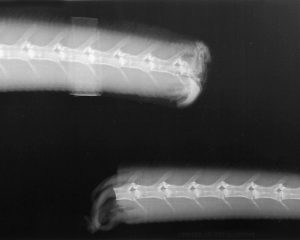

尾椎の腹側に血液とリンパ管が見られます。尾椎動脈は椎骨に近いところを走行し、尾椎静脈は動脈の腹側に位置し、動脈と静脈の両側に1対の大きなリンパ管があります〔lepen et al.1995〕。尾椎には予め形成された骨折線(離脱面)があり、この部分が離開することで自切します。

自切は複雑な防御メカニズムで、尾を掴んだり、捕食者につかまったり、何らかの方法で挟まれたりすると、尾の筋肉群の収縮によって離脱面に負荷がかかり、尾椎が離断します。 離断は通常、トカゲがつかまれた部分の直前、またはこれより前の3つ以下の椎骨で発生します。

周囲の筋肉群は瞬時に分離するように配置され、 尾骨動脈も破断点で収縮するため出血は最小限で収まり、周囲の筋肉の収縮によっても止血されます〔Arnold 1984〕。